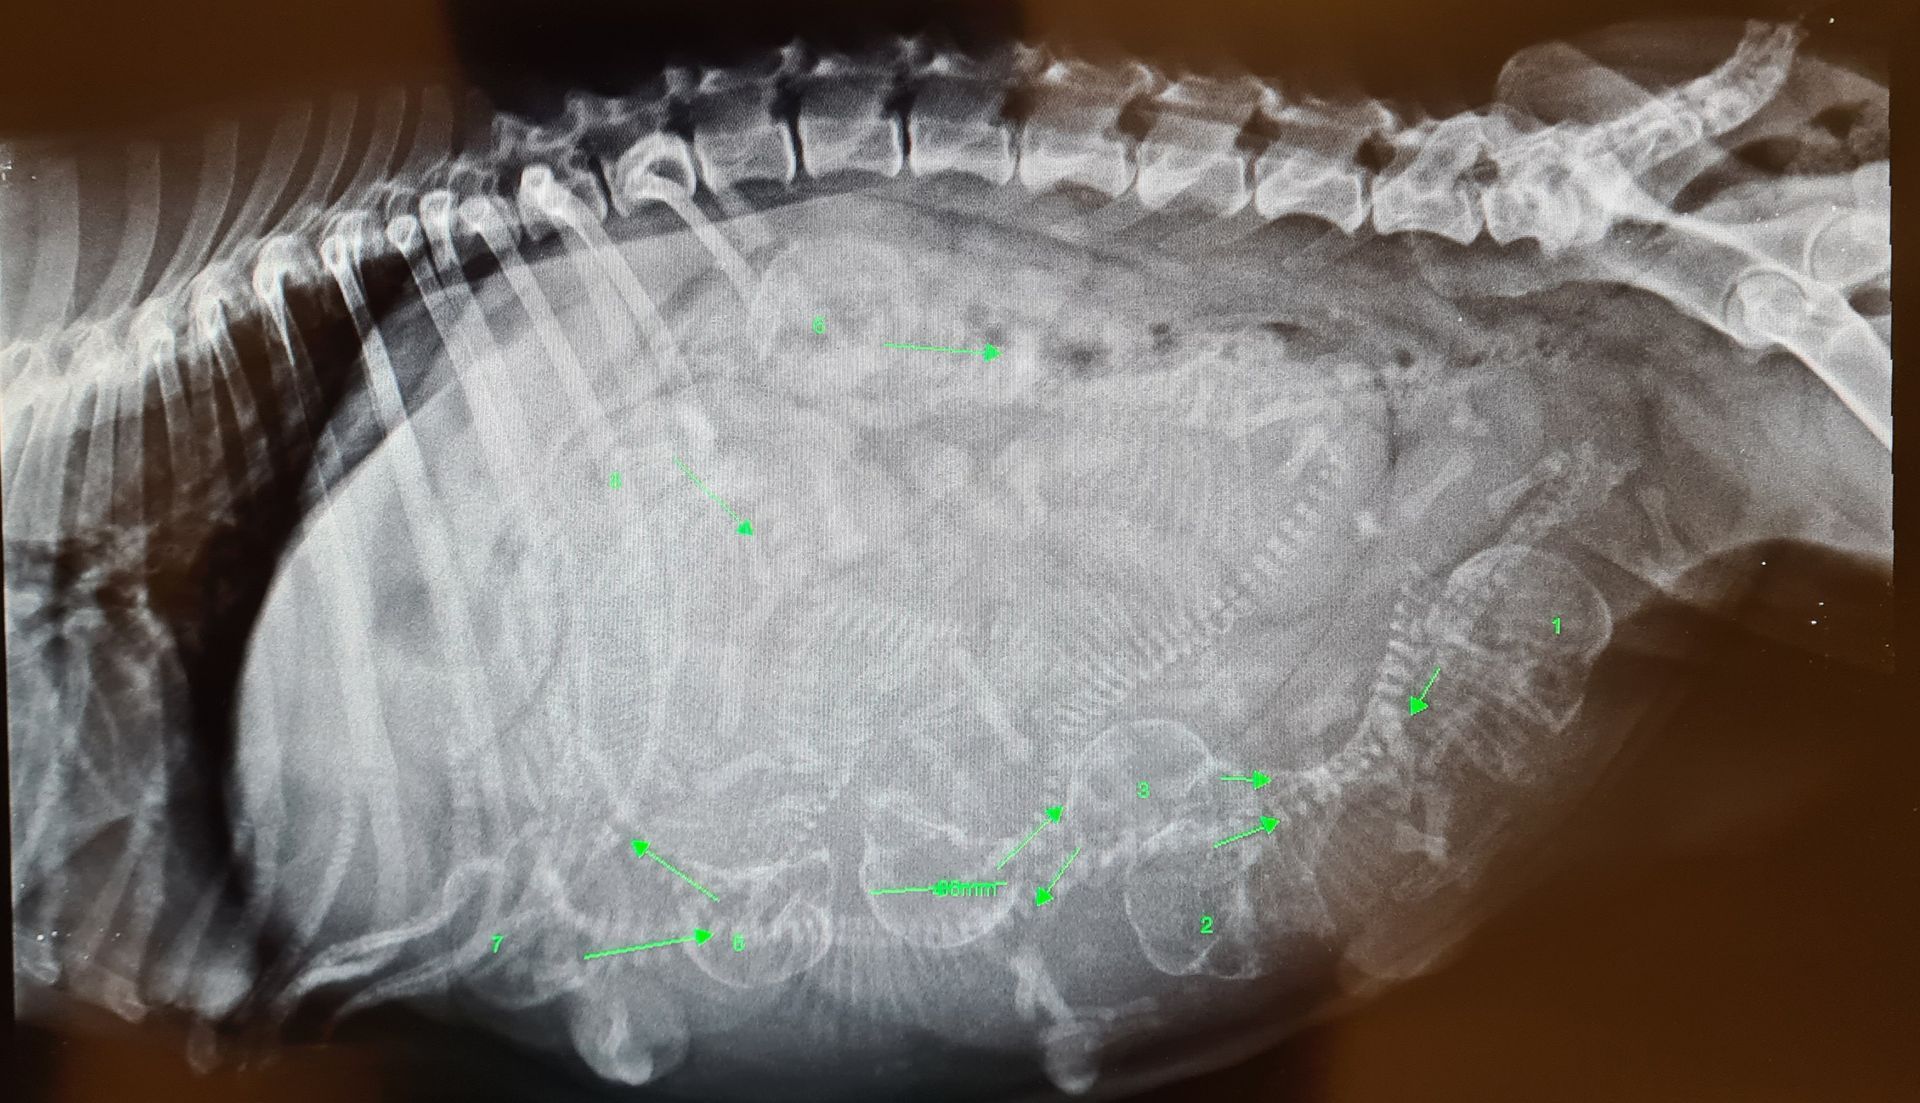

La radiologie

La clinique est équipée d'un générateur radio ainsi que d'un développement numérique. Ce type de développement est rapide, sans utilisation de produits chimiques et permet d'obtenir les images sur un écran d'ordinateur. La définition des radios est ainsi meilleure. Nous pouvons aussi facilement vous faire parvenir les radios de votre animal ou les transférer à un confrère le cas échéant par mail.

- Radios classiques

- Radios avec produit de contraste